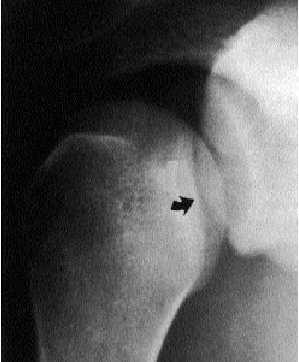

La radiografía A-P de hombro es la principal causa de que esta luxación quede sin diagnosticar en la fase aguda, circunstancia que se produce, según series, entre el 60% y el 79% de los casos. En efecto, la radiografía A-P puede ser muy similar a la de un hombro normal, y si no se ha sospechado la luxación por la clínica no se podrán buscar los signos radiológicos que permiten confirmar el diagnóstico:

1) La cabeza humeral y la cavidad glenoidea no se superponen (signo de la hendidura).

2) La elipse regular y redondeada de solapamiento entre la cabeza humeral y la cavidad glenoidea es más pequeña, irregular o está desplazada (signo de la cavidad glenoidea vacía) (fig. 6).

Fig. 6. Signo de la cavidad glenoidea vacía.

3) Desaparición del perfil del cuello humeral al estar el húmero en rotación interna completa.